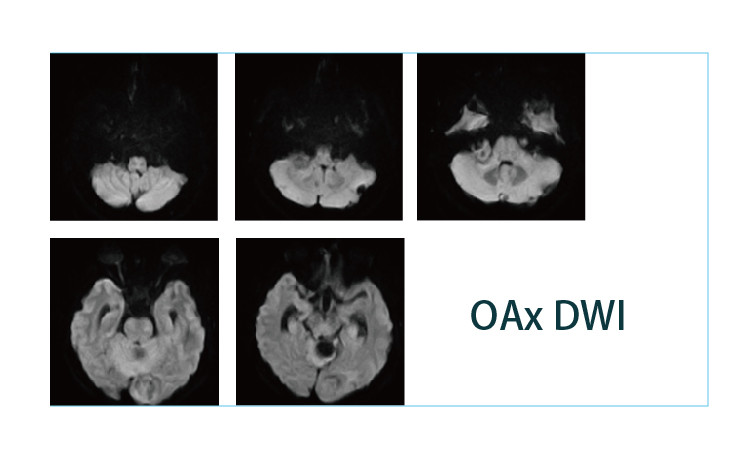

【朗润影像档案】20190412磁共振影像病例结果讨论